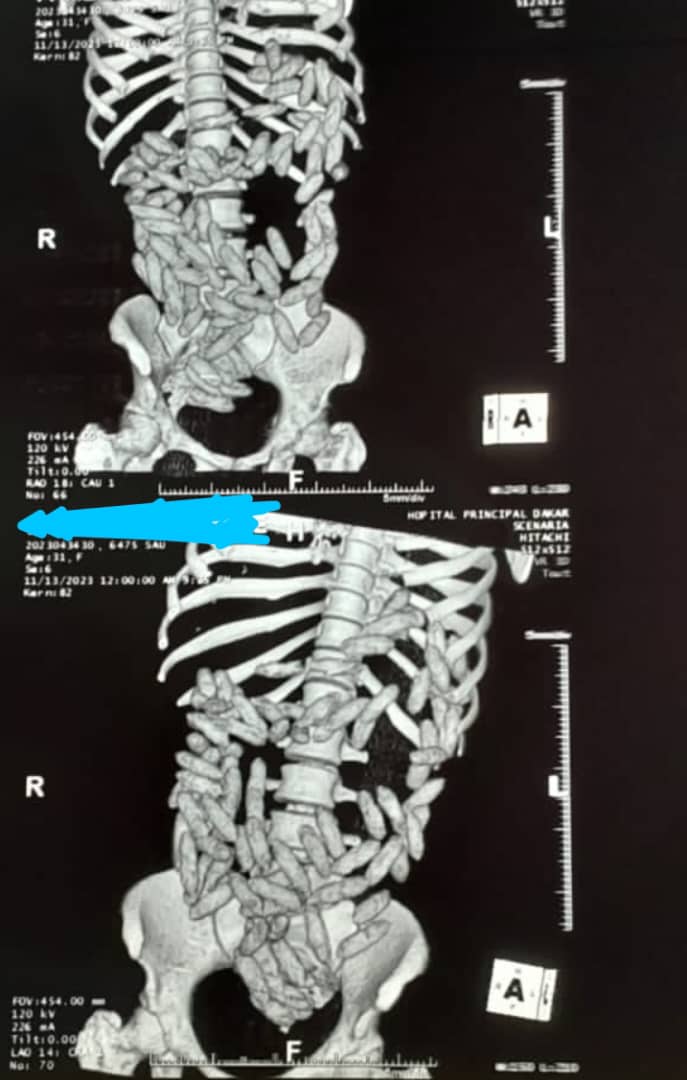

Le scanner effectué par le Médecin de garde a permis de constater la présence de boulettes dans l’estomac de la mule. Selon ses déclarations, elle en aurait ingurgité cent (100). Entre son admission à l’hôpital, le lundi et ce mardi 14 novembre 2023 à 17

heures, la dame a eu à expulser 92 boulettes testées positives à la cocaïne par le Laboratoire national d’Analyse des Drogues (LINAD) de la Police technique et scientifique. Elle est toujours en surveillance à l’HPD.